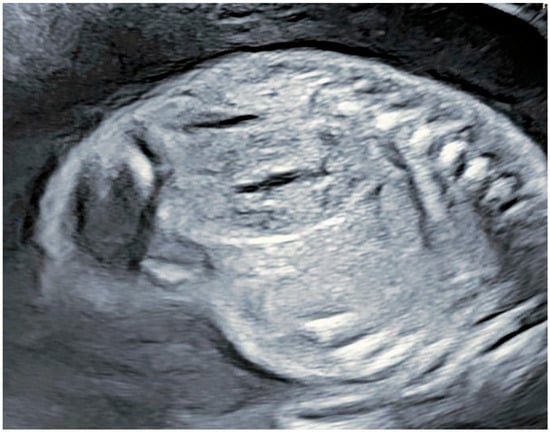

2. Case Presentation

Patient Information